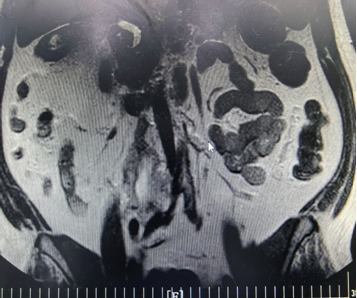

对于新发现的异常病灶,家属异常焦虑。核磁增强检查后,主管医生与磁共振室雷晓燕主任进行沟通,雷主任对影像学资料认真分析后提供检查报告,腹部MRI增强示:约腰3﹣低1水平下腔静脉﹣腹主动脉右旁腹膜后异常信号影,倾向良性病变可能,并通过电话将各种可能病灶进行分析。当大家正欢聚一堂享受新年的喜悦时,科室为患者的明确诊断进行多学科团队线上讨论。大年初一,磁共振室雷晓燕主任、普外科迟达超主任医师、肿瘤外科曹伟副主任医师、内分泌科张瑜庆副主任医师线上为患者的进一步后续治疗提供诊疗建议。一周时间内,所有的检查化验均进行完毕。该患者术后病理为(腹膜后)节神经瘤,体积12cm*7cm*4cm。患者特意送来锦旗表示感谢。

节细胞神经瘤是一种罕见的起源于锥体旁神经丛周围的原始神经嵴组织的良性肿瘤,可发生在全身各个部位,常见部位包括后纵隔(41.5%)、腹膜后(37.5%)和肾上腺(21%),发生于腹膜后的节细胞神经瘤占原发性腹膜后肿瘤的0.72%~1.60%。腹膜后节细胞神经瘤完整切除的患者预后良好,包绕血管的肿瘤手术难度大,导致不能完整切除。